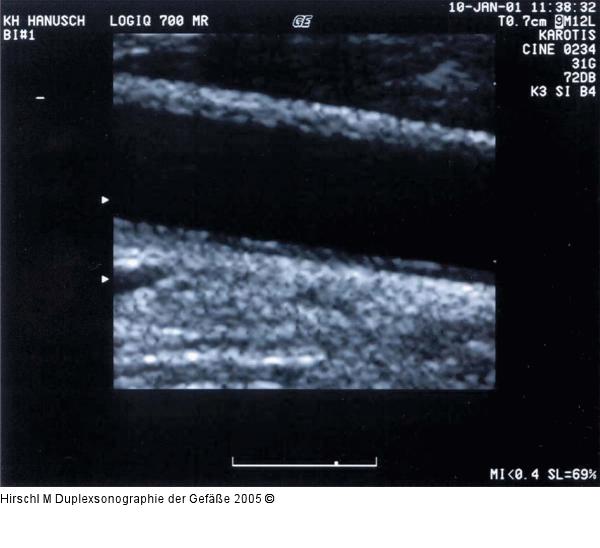

Abbildung 3: Duplexsonographie - Karotis Einstellung der Fokuszone zur Darstellung der Intima-Media-Dicke an der Hinterwand einer A. carotis communis in Halsmitte |

Einstellung der Fokuszone zur Darstellung der Intima-Media-Dicke an der Hinterwand einer A. carotis communis in Halsmitte |